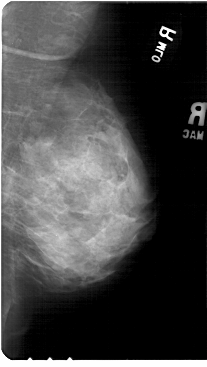

A_1852_1.LEFT_MLO

LEFT_MLO LINES 5491 PIXELS_PER_LINE 3121 BITS_PER_PIXEL 12 RESOLUTION 43.5 OVERLAY

FILE: A_1852_1.LEFT_MLO.OVERLAY

TOTAL_ABNORMALITIES 1

ABNORMALITY 1

LESION_TYPE CALCIFICATION TYPE PUNCTATE DISTRIBUTION CLUSTERED

ASSESSMENT 4

SUBTLETY 2

PATHOLOGY MALIGNANT

TOTAL_OUTLINES 1

BOUNDARY